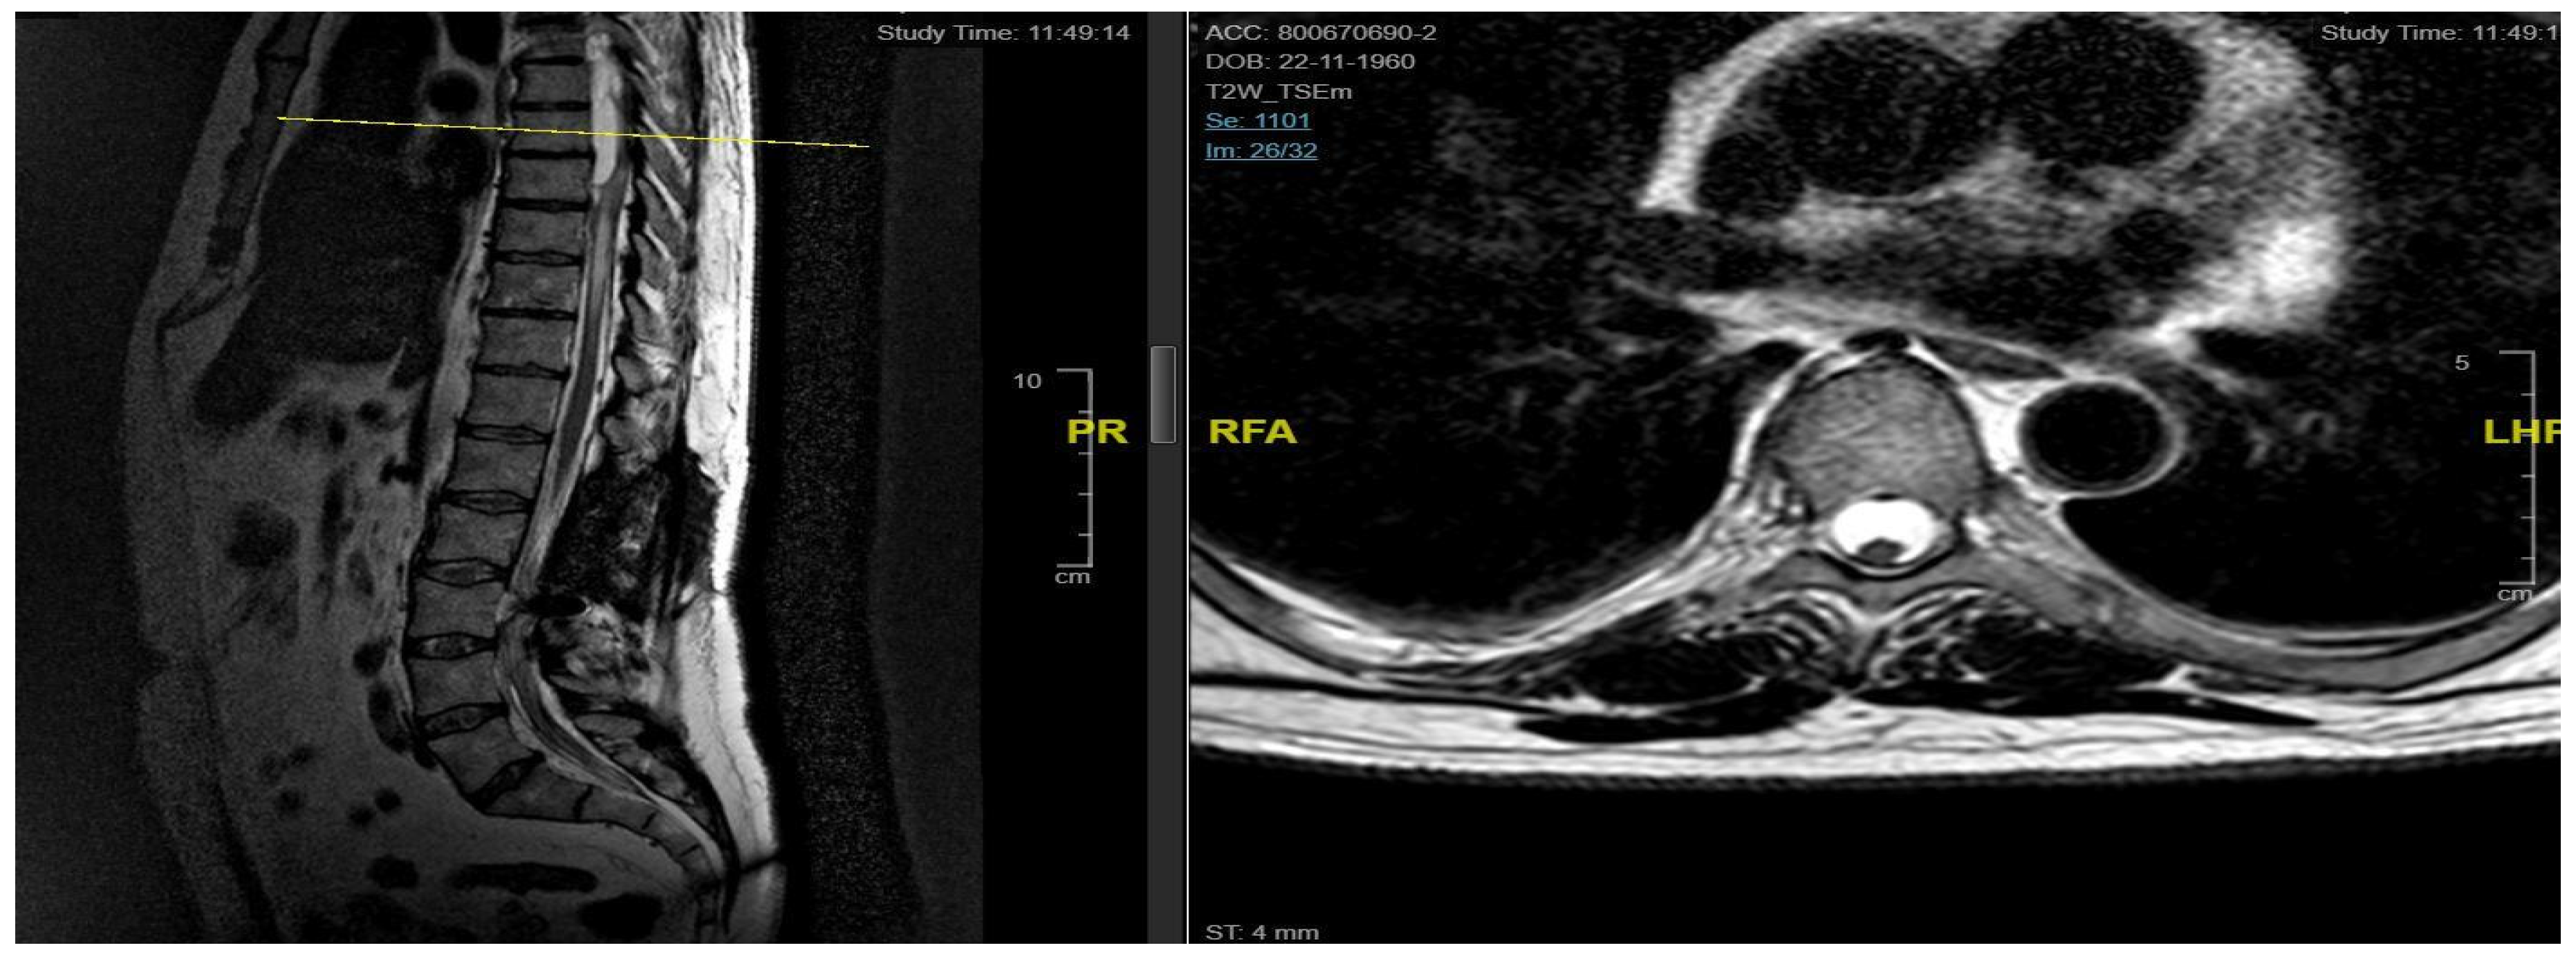

3.4.5. Case 5

| Level | T12–L2 | C5–C6 | T7–T10 | T8–T9 | T8–T11 |

| Location | Intramedullary | Intradural | Intradural–Extradural | Intramedullary | Intradural |

| Surgical treatment | lysis of adherences and syrinx cavity opening | resection of the cystic formation and adhesiolysis | resection of the cystic formation and adhesiolysis | resection of the cystic formation and adhesiolysis | resection of the cystic formation and adhesiolysis |